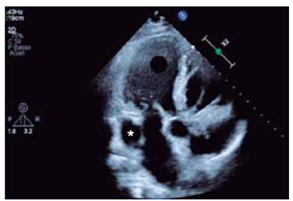

A estrutura indicada pelo asterisco na figura a seguir pode estar associada a

(Arquivo pessoal; imagem utilizada com autorização)

Provas